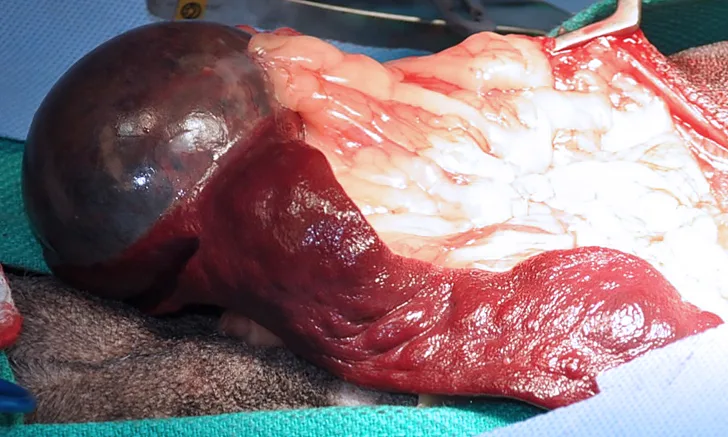

If adequate margins cannot be achieved with a wide excision of STS, consideration should be given for marginal or radical excision. Radical excision is the removal of an entire anatomical segment (eg, limb amputation). Many antebrachial STS can be successfully removed without amputation by employing wide excision with antebrachial fascia as the deep barrier. This defect can be reconstructed with a free skin graft or another skin-reconstruction technique2 (Figure 1). If the mass is overlying the carpus or elbow, a marginal excision should be considered. In low- and intermediate-grade tumors and geriatric patients, this may be sufficient for long-term control.3 For high-grade tumors (III), consideration should be given to follow up with radiation therapy.4

(A) Antebrachial soft-tissue sarcoma that is treated with wide resection. Note the deep layer of antebrachial fascia that serves as the deep margin and a barrier to tumor cell invasion (arrow). The surgeon’s fingers to the right of the arrow are between the extensors of the antebrachium and the fascial layer that is deep to the tumor. (B) Reconstruction of defect after antebrachial soft-tissue sarcoma wide resection with a free skin graft